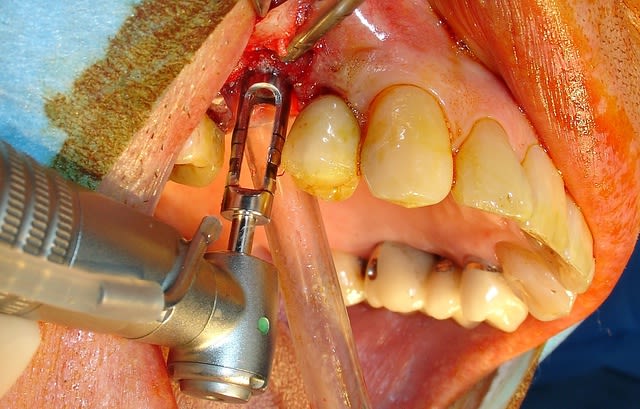

J'ai donc choisi cette dernière solution très rapide.

Le remplacement c'est fait par un AnyRidge de chez MegaGen de diamètre 5 et longueur 10. J'ai juste profiter de la situation pour re-combler là ou en 2007 on avait mis de l'os autogène....mais ou est il passé? Le comblement a été fait avec une recette maison à base de PRF os bovin et bétaTCP.